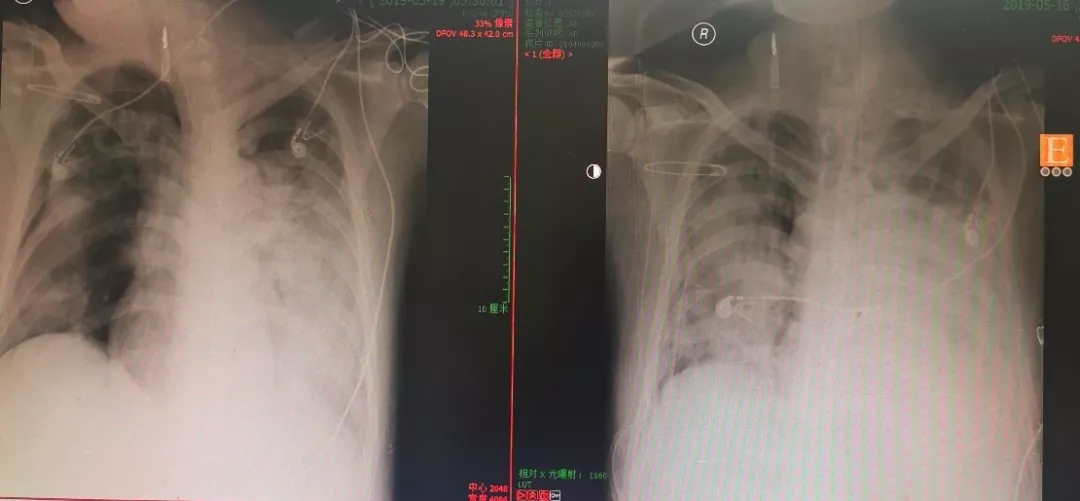

原先担心血小板继续降低,会不会颅内出血,CT检查得以排除。但是复查的肺部CT显示感染的面积明显扩大,而且病情进展的速度快得惊人。也难怪会出现如此的病情变化。

因为在凌晨3:30,住院总还是忙活了一阵。再度出现的呼吸窘迫,让肌松药物重新调整了剂量。再一次拍摄了床边胸片,气胸还有一点,但是些许安慰的是肺部的透亮度有所好转。

上午10:38,病房的同事说情况又开始走下坡路,氧饱和度直降至70%。再次的床边胸片提示了右肺新发的气胸,而且有可能导致的肺压缩很严重。

十分钟后,在同桌千穿百孔的右肺上又多了一根管子,对侧左肺几乎是白色的,或许早已不工作。下面连接的引流瓶又多了一个,负压吸引带来的水泡翻滚声又升高了许多分贝。